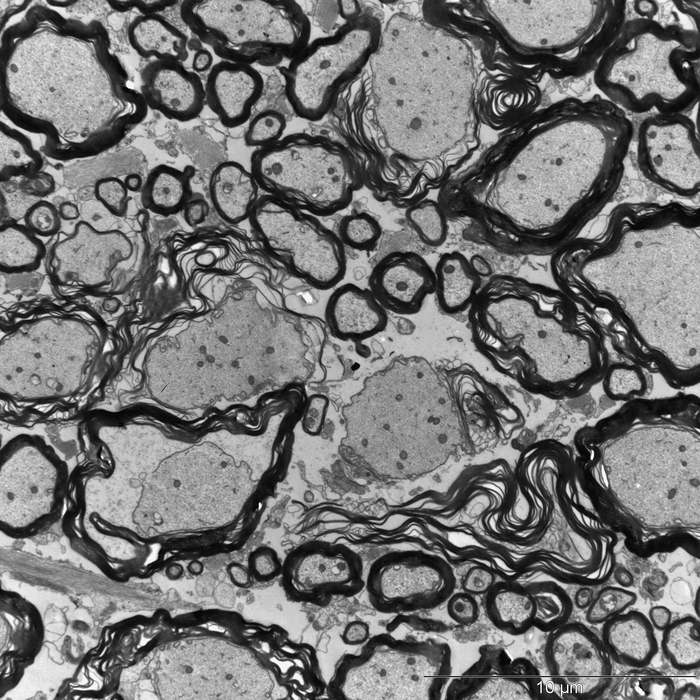

And the researchers did indeed find what they were looking for: When they administered the cow's milk constituent casein together with an effect enhancer to the animals, the mice went on to develop neurological disorders. Electron microscopy showed damage to the insulating layer around the nerve fibers, the myelin. The fat-like substance prevents short circuits and additionally significantly accelerates stimulus conduction.

Perforated myelin layer

In multiple sclerosis, the body's immune system destroys the myelin sheath. The consequences range from paresthesia and vision problems to movement disorders. In extreme cases, patients need a wheelchair. The insulating sheath was also massively perforated in the mice - apparently triggered by casein administration. "We suspected that the reason was a misdirected immune response, similar to that seen in MS patients," explains Rittika Chunder, who is a postdoctoral fellow in Prof. Kürten's research group. "The body's defenses actually attack the casein, but in the process they also destroy proteins involved in the formation of myelin."